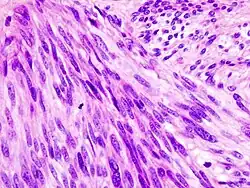

Stromacellen of mesenchymale stromacellen (MSC) zijn differentiërende cellen die in overvloed voorkomen in het beenmerg, maar ook overal in het lichaam voorkomen. De term stroma komt van het Latijnse stromat-, "bedbedekking", en het Oudgriekse στρῶμα, strôma, "bed". Stromacellen kunnen zich ontwikkelen tot bindweefselcellen van elk orgaan, bijvoorbeeld in het baarmoederslijmvlies, de prostaat, het beenmerg, de lymfeklieren en de eierstokken. Het zijn cellen die de functie van de parenchymcellen van dat orgaan ondersteunen. De meest voorkomende stromacellen zijn fibroblasten en pericyten. Ook een telocyt is een soort interstitiële stromacel met zeer lange (tientallen tot honderden micrometers) en zeer dunne uitlopers, genaamd telopoden.[1]

Stromacellen spelen een belangrijk rol in de immuunrespons van het lichaam en moduleren ontstekingen via meerdere routes. Ze helpen ook bij de differentiatie van hematopoëtische cellen en de vorming van noodzakelijke bloedbestanddelen. Het is bekend dat de interactie tussen stromacellen en tumorcellen een belangrijke rol speelt bij de groei en progressie van kanker.[2] Bovendien is beschreven dat stromacellen in het beenmerg betrokken zijn bij menselijke hematopoëse en ontstekingsprocessen door lokale cytokinenetwerken (bijv. M-CSF,[3] LIF[4]) te reguleren.